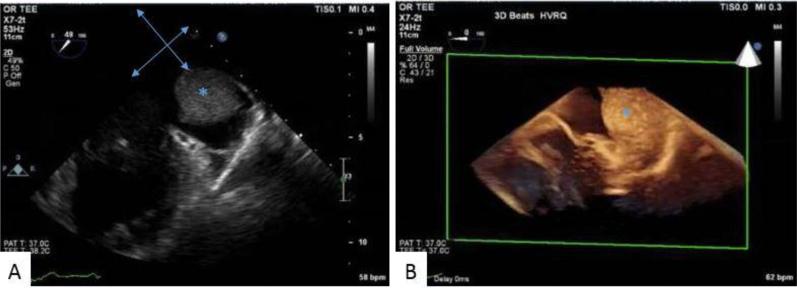

Epicardial Cavernous Hemangioma: A Diagnostic Challenge.

• Primary cardiac tumors, although rare, represent a wide differential diagnosis. • It is often difficult to decipher the type of tumor from imaging alone. • This case highlights imaging modalities to plan surgical removal of cardiac masses.

• 本病例重点介绍了用于规划心脏肿块手术切除的影像学检查方法。